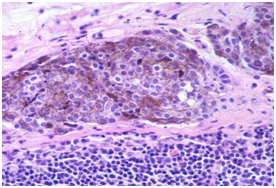

- Cervical lymph nodes with inclusions of salivary glands may exhibit expansive, reactive lymphoid follicles with prominent germinal centres with numerous tingible body macrophages, foci of monocytoid cells, immunoblasts, plasma cells and vascular proliferation. Disseminated inclusions of salivary gland ducts and acini may not manifest lymphocytic permeation and destruction, as is exemplified in Sjogren’s syndrome and Mikulicz’s disease (Figure 2 - Figure 4).3

- Salivary glands inclusions: Inclusions from the salivary glands are frequent in the upper cervical lymph nodes and may manifest as a component of the developmental embryogenesis. Intact, undamaged glandular ducts and acini may be elucidated. The lymph node may manifest reactive follicles with prominent germinal centres with numerous tingible body macrophages, plasma cells and monocytoid cells. The concordant sjogren’s & mikulicz syndrome may depict a lymphocytic infiltration of the ducts and acini.4 A malignant transformation may emerge with these inclusions, usually as a potential warthin’s tumour, a pleomorphic or a monomorphic adenoma, a mucoepidermoid carcinoma or an acinic cell carcinoma.5

Figure 2 Nevus cell inclusions containing melanin.